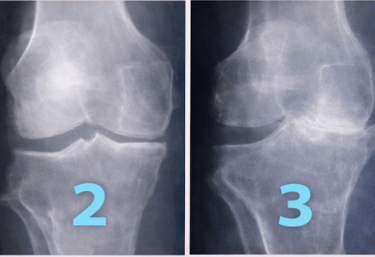

¿Tu rodilla se ve asi?

La degeneración avanza por 4 grados, no dejes que tu rodilla llegue a su ultima instancia donde la única solución es el reemplazo con PROTESIS DE RODILLA